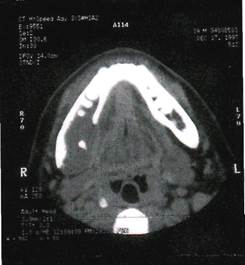

Клиника. Миксома (миксофиброма) растет медленно, безболезненно, проявляется вздутием кости. Пальпаторно определяется плотное, безболезненное выпячивание челюсти с гладкой поверхностью. Слизистая оболочка над опухолью в цвете не изменена. Зубы в границах новообразования подвижные, смещаются. При локализации патологического очага вблизи нижнечелюстного канала возникает симптом Венсана. На верхней челюсти миксома может прорастать в верхнечелюстную пазуху и полость носа.

Рентгенологическая картина. Определяется очаг деструкции костной ткани с нечеткими границами. В некоторых случаях может иметь вид мелких ячеистых образований, разделенных костными перегородками.